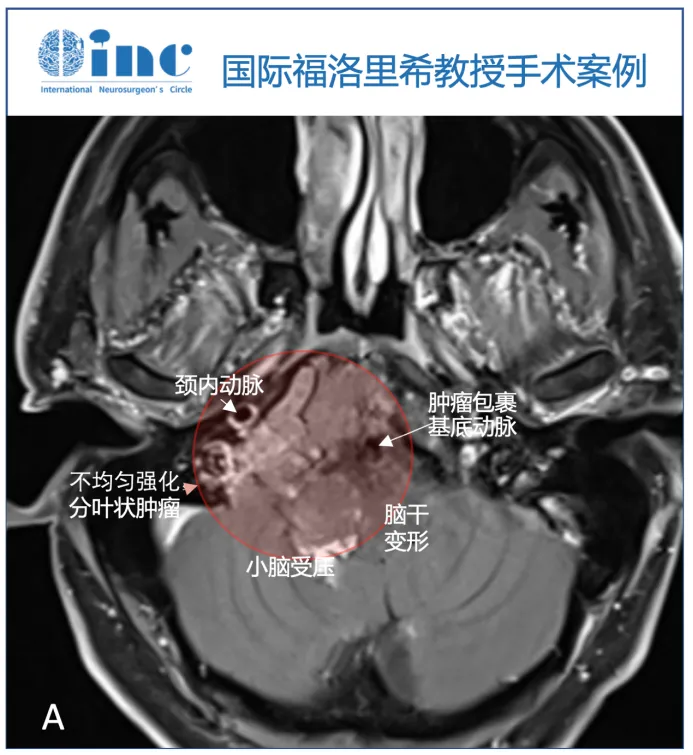

脑MRI检查显示颅颈交界处巨大轴外病变,提示脊索瘤,T1WI等强度,T2高强度,不均匀增强,以右侧岩斜坡软骨联合为中心,向下延伸至颅颈交界处,硬膜内延伸至Luschka孔,压迫脑干。肿瘤压迫小脑的最后部分也有增强,提示该部分肿瘤的颅底浸润和颅底血管化。右侧枕髁被肿瘤浸润并完全占据。由于肿瘤向外侧、硬膜内浸润生长,血管包膜和颅底浸润,内镜下鼻内入路被认为风险较高,实现完全切除的机会有限。

▼术前MRI显示轴内-轴外肿瘤,累及斜坡和颅颈交界处,压迫脑干致脑干移位,为不均匀增强(图A)。